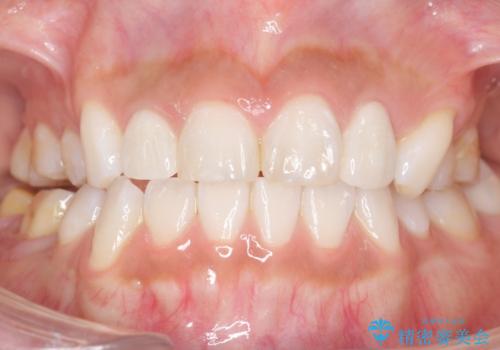

- 奥歯の隙間を治したいとご希望された患者様です。

学生時代に舌側矯正されていたものの、通院が大変になり治療を途中でやめてしまい、奥歯の間に隙間が残ってしまったそうです。

矯正せずに早く治したいという強いご希望とう蝕があることから、セラミッククラウンによる補綴治療で隙間を閉じることにしました。

矯正せずに隙間を閉じることができ、ご満足頂けました。

セラミッククラウンの審美的な仕上がりと咬み心地に喜んで下さいました。